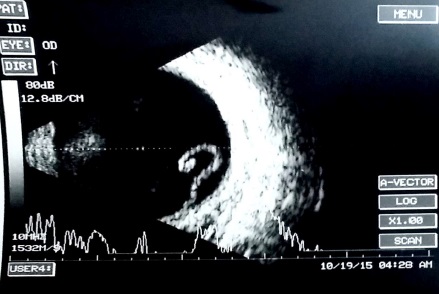

Ultrasonographic features of choroidal detachment (CD)

A CD is denoted by a round mound which is limited by the strong uveoscleral attachments (scleral spur, vortex veins, and optic nerve). It has limited mobility and an A scan passing perpendicularly through a CD shows 'M' (double peak) shape. The shape is typically of a smooth dome, usually not attached to the optic disc. The fluid in the suprachoroidal space may be anechoic (serous CD) or have mild to moderate amplitude point echoes (hemorrhagic CD). When CDs touch each other they are called kissing choroidals, and such cases may be more prone to permanent adhesion and may guide the timing of surgery in suprachoroidal hemorrhage. USG also notes the clot lysis in suprachoroidal hemorrhages and guides timing of surgery, and the location of the suprachoroidal hemorrhage guides the area of drainage.